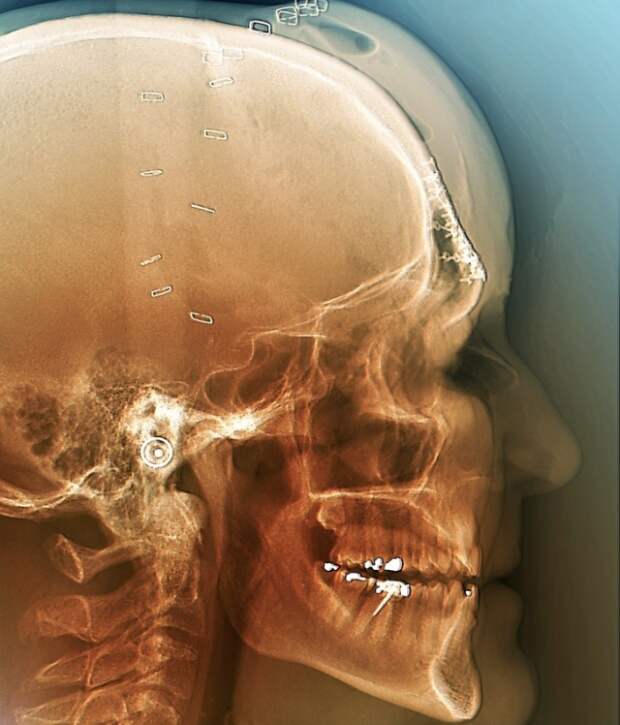

15. Этот снимок сделан после операции по восстановлению черепа. Человек пострадал в ДТП